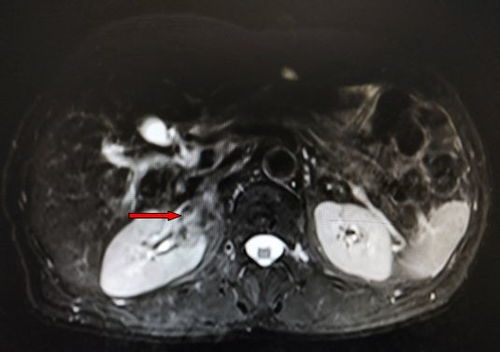

肝癌(特别是肝内胆管癌)

- 肝癌中的“硬骨头”:尤其胆管癌,诊断时多已晚期;

- 治疗选择少:手术、放化疗效果有限,靶向/免疫治疗尚未完全明确;

- 肝功能限制:患者常合并肝硬化、门脉高压,治疗受限。